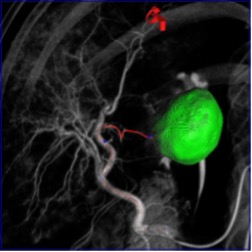

В 2010 г. F. Deschamps et al. впервые представили технологии определения питающих опухоль сосудов и внутрисосудистой стереотаксической навигации в режиме реального времени (режиме дополненной рентгеноскопии) предназначенные для проведения суперселективной катетеризации и суперселективной трансартериальной химиоэмболизации (ссТАХЭ) узлов ГЦР [19]. Использование этих технологий принципиальным образом повысило точность выявления питающих узлы ГЦР артерий, скорость их катетеризации, равномерность эмболизации и, как следствие эффективность ссТАХЭ, что было подтверждено рядом крупных исследований [20, 21]. В метаанализе 2024 г. было убедительно показано, что использование этих технологий привело к трехкратному увеличению общей трехлетней выживаемости пациентов, страдающих ГЦР, по сравнению с пациентами, получающими ссТАХЭ только под контролем цифровой субтракционной ангиографии (ЦСА) [22]. Аналогичные данные были продемонстрированы и в азиатских группах пациентов, получавших ссТАХЭ с использованием и без использования визуализационных и навигационных ПДКТ-технологий [23], а также в ряде отечественных исследований [24, 25]. В настоящее время технологии внутрисосудистой навигации и другие технологии слияния изображений и 3D-роадмаппинга широко используются также для эмболизации доброкачественных опухолей (например, для лечения доброкачественной гиперплазии предстательной железы), артериовенозных мальформаций, поиска артерий, являющихся источником кровотечения, установки стент-графтов, эмболизации эндоликов после стентирования и многих других целей [26].

2.2. Эндоваскулярная навигация